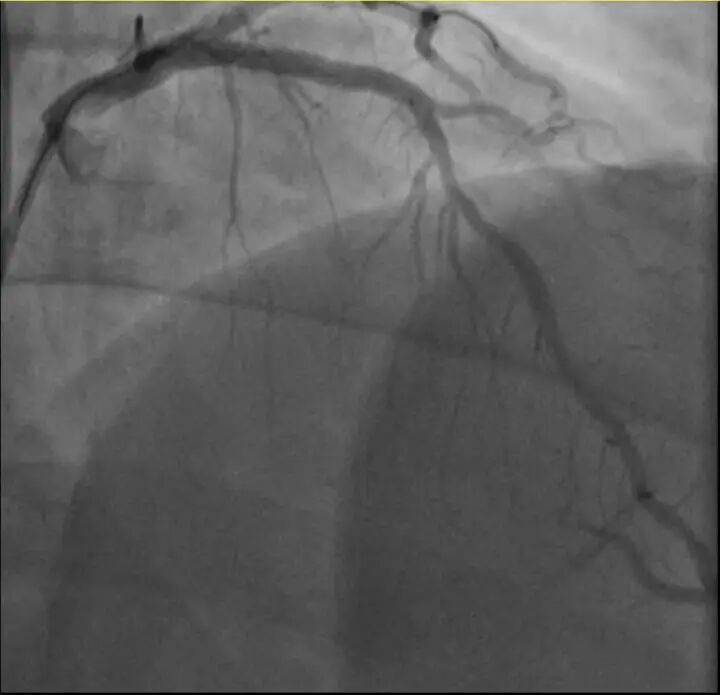

参与医治后影象图

浙江病院心(xin)血管内科的(de)医生分(fen)析,剧烈(lie)运动致(zhi)使这位患者心(xin)脏的(de)没有波动斑块碎裂,进(jin)而造成前降支近段次全闭塞。所幸送医及时(shi),孙先生的(de)身材险情被化解。